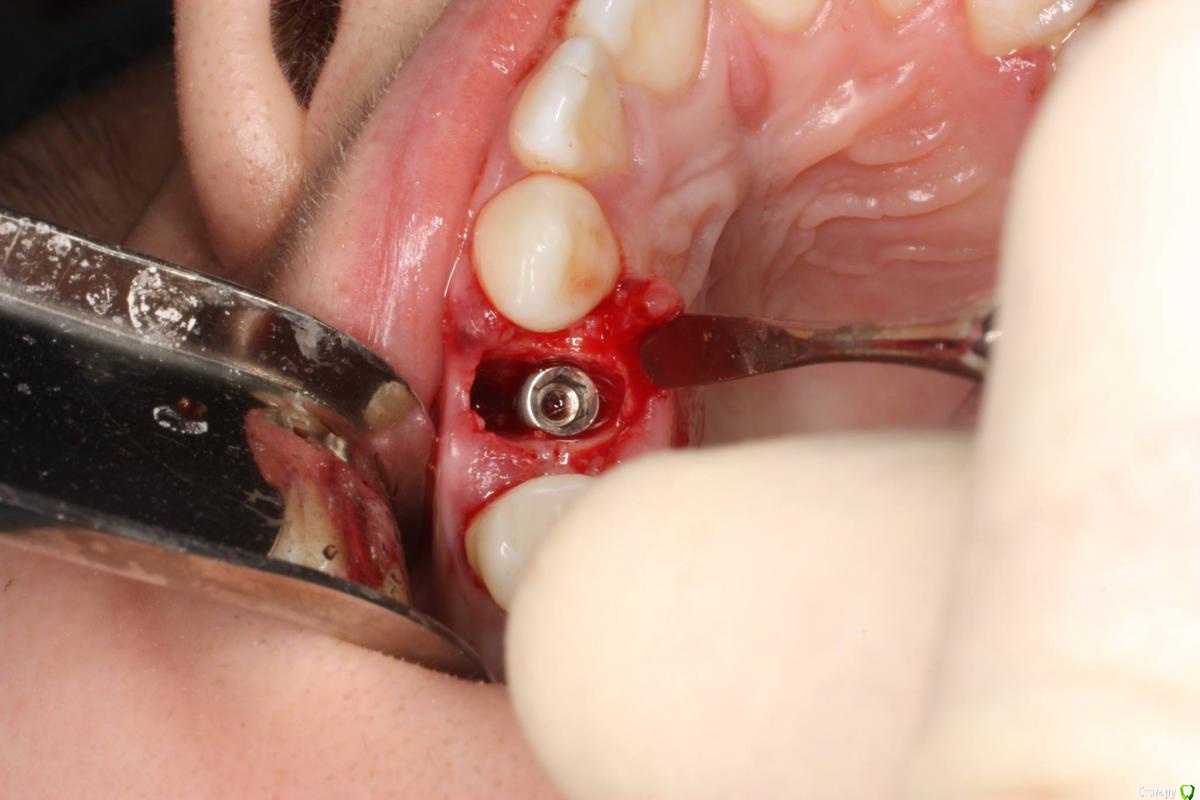

togrul Опубликовано 24 ноября, 2016 Поделиться Опубликовано 24 ноября, 2016 Имплантация проводилась 6 месяцев назад . Пациентка запротезирована. Это моя 2 имплантация была . 7 Ссылка на комментарий

togrul Опубликовано 24 ноября, 2016 Автор Поделиться Опубликовано 24 ноября, 2016 Нет Bio oss использовали . Ссылка на комментарий

syrovovec Опубликовано 24 ноября, 2016 Поделиться Опубликовано 24 ноября, 2016 Графт может и не особо нужен, а сст просится Ссылка на комментарий

АнтонТЛТ Опубликовано 24 ноября, 2016 Поделиться Опубликовано 24 ноября, 2016 Не вижу показаний для сст, коронкой на раз всё отожмётся 2 Ссылка на комментарий